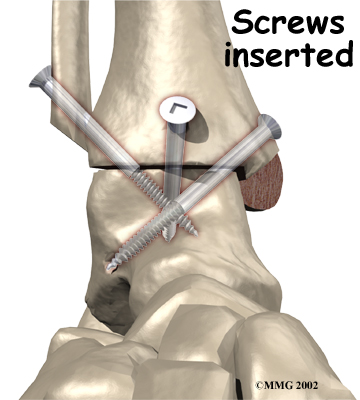

It is important when the surfaces are removed that the angles of the cut surfaces are correct. When the tibia is brought against the talus, the foot should be at a right angle to the lower leg. Once the cuts are made the bones must be held in place while they fuse. This can be done using large metal screws and metal plates if necessary. The screws are usually under the skin and are not removed unless they begin to rub and cause pain.